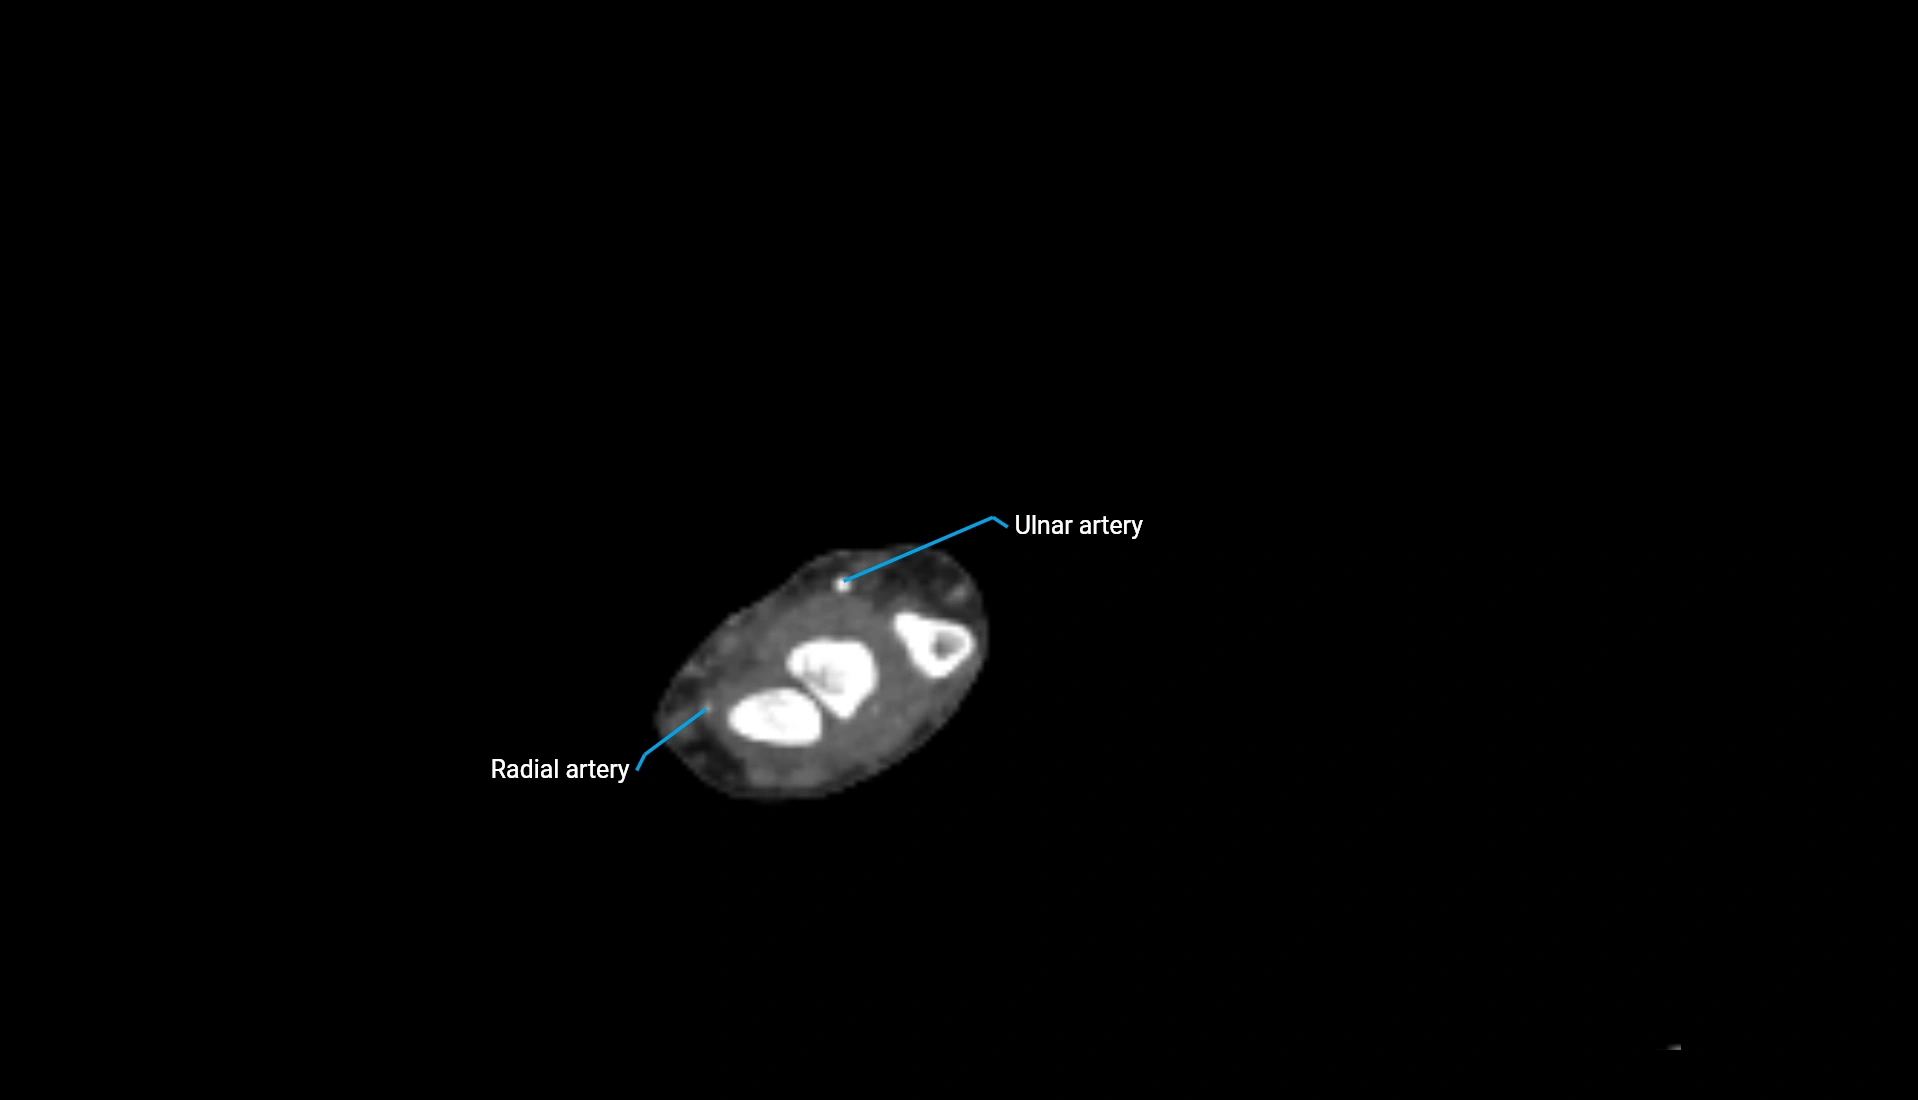

MRI image

image